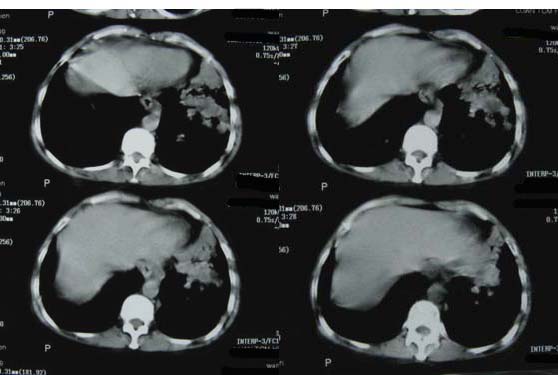

肝癌、肺转移。

1双肺支气管扩张  2双肺多发块状影,考虑:转移瘤;3肝门区圆形软组织影,先考虑:转移淋巴结可能性大.

肝癌、肺转移 支持

1、肺转移;

4、建议肝脏增强检查。

3、建议肝脏增强检查

1双肺多发块状影,考虑:转移;2双肺支气管扩张;3建议肝脏增强检查。

1肺转移瘤 2肝门区圆形软组织影,考虑淋巴结转移